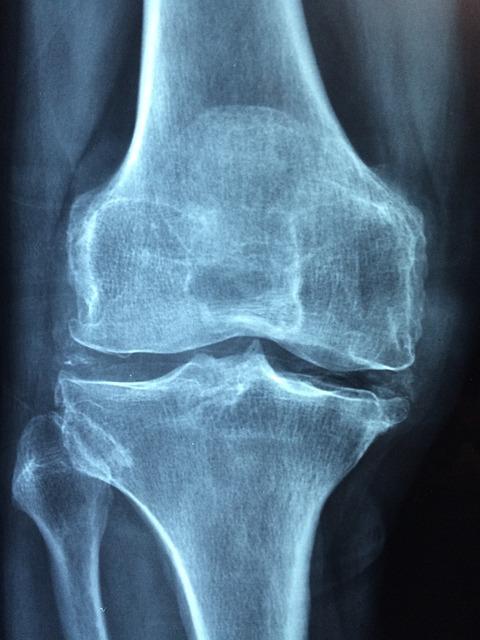

Osteoarthritis: This is the most common form of arthritis. It occurs when the protective cartilage that cushions the ends of your bones wears down over time.